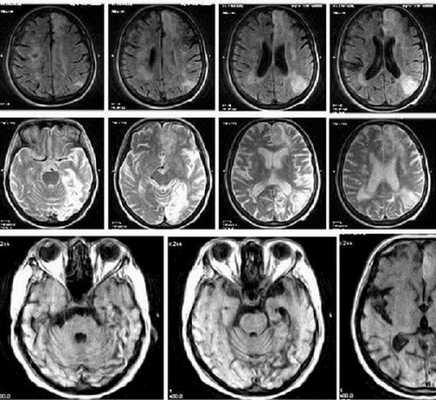

Серия снимков МРТ при подозрении на инсульт

Для визуализации состояния церебрального вещества и сосудов головного мозга используют индукционное поле. Под действием направленного электромагнитного импульса атомы водорода в молекулах воды меняют положение, возвращаясь затем на место. Резонанс заряженных частиц фиксируют при помощи чувствительных датчиков и обрабатывают посредством сложных программных алгоритмов.

В острейшем периоде (первые 6 часов) проводят диффузно-взвешенную (ДВ) МРТ. Полученные снимки отражают патологические изменения мозгового вещества через 5 минут после появления признаков инсульта. ДВ-изображения помогают определить область поражения, показывают отек тканей вокруг очага, смещение церебральных структур.

Острый период (1-7 день) характеризуется появлением четко ограниченных светлых участков на МРТ в Т2-взвешенном режиме. На Т1 ВИ очаги некроза имеют гипоинтенсивный сигнал.

Головной мозг на МРТ при разных режимах сканирования